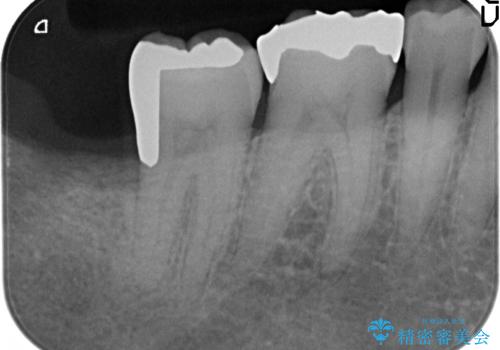

- 右下奥歯がたまにしみるので診て欲しいといらっしゃった方の症例です。

右下7番目の歯の歯茎より深い位置に虫歯があったため、親知らずを抜歯後PGA(ゴールド)インレーによる修復を行いました。